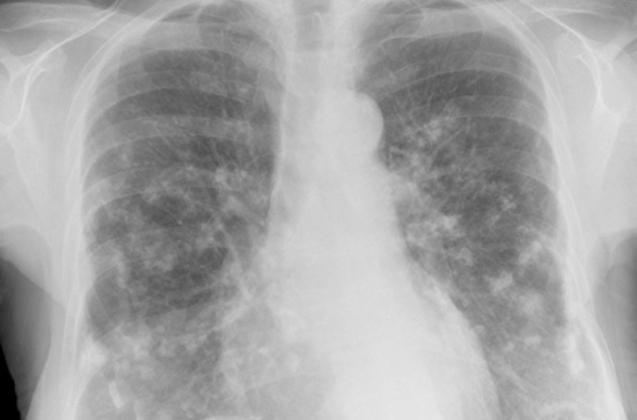

Key Signs and Subtle Hints of Mesothelioma On Cxr

While a CXR isn't definitive, certain findings can raise a red flag for "Mesothelioma On Cxr" and prompt further investigation. Radiologists are trained to look for patterns that, while not exclusive to mesothelioma, are highly suggestive, especially in patients with a history of asbestos exposure.

These signs often relate to changes in the pleura, the thin membrane surrounding the lungs. It's about looking for unusual textures, fluid patterns, or shifts in lung volume. Here are some of the key indicators that might lead to suspicion:

- **Pleural Thickening:** This is one of the most common signs. It can appear as irregular, nodular, or diffuse thickening of the pleura, often encasing the lung. This is different from benign pleural plaques.

- **Pleural Effusion:** Fluid accumulation in the space between the lung and chest wall is very common with mesothelioma. It's often large, persistent, and may recur quickly after drainage, even post-procedure.

- **Volume Loss of the Affected Lung:** As the tumor grows and constricts the lung, it can lead to a decrease in lung volume on the affected side, sometimes pulling structures like the trachea towards it.

- **Calcified Pleural Plaques:** While not mesothelioma itself, these calcifications indicate past asbestos exposure and significantly increase the suspicion for mesothelioma if other more active signs are present.

- **Unilateral Diaphragmatic Elevation:** One side of the diaphragm may appear unusually high due to tumor involvement or significant volume loss in the lung above it.